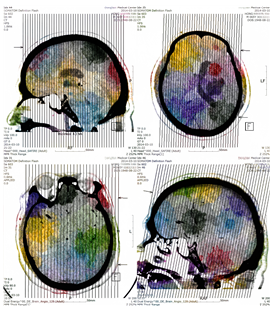

첫 개인전에는 직장 동료들과 지인들이 많이 왔었다. 신분증, 여권, 신용카드의 이미지가 혼란스럽게 중첩된 작품이 걸린 전시에 온 그들은 의아해하는 표정이었다. 아마도 멋진 풍경이나 인물 사진을 기대하고 온 것일지도 모르겠지만 그런 기대를 여지없이 허무하게 만들어 버렸으니, 나로서는 기뻤던 기억이 난다. 그리고 사진이라는 고정 관념에 조금은 균열을 일으키는 것 같아서 작은 성과를 느낄 수 있었다. 지금 생각해 보면, 미술을 전공하지 않았지만, 운이 좋게도 그 첫걸음을 잘 디뎠다는 생각이 든다. 그리고 다시 말하지만, 여서 만나 뵙고 배움의 기회를 주신 많은 스승들께서 나의 세포와 감각을 잘 단련시켜 주신 덕분이 아닐까 하는 생각이 들었다. 《Digital Being》에서 선보였던 작품 중에 의료용 이미지를 가지고 작업한 작품이 확장되어 다음 전시인 《Homo Ludense》로 이어지는 기회를 가질 수 있었다.

1251_2597_4743.png

홍준호, Homo Ludense #02, 2016, Digital Inkjet Pigment Print(Mixed Medical CT and Water Color on Hanji), 86x76.4cm